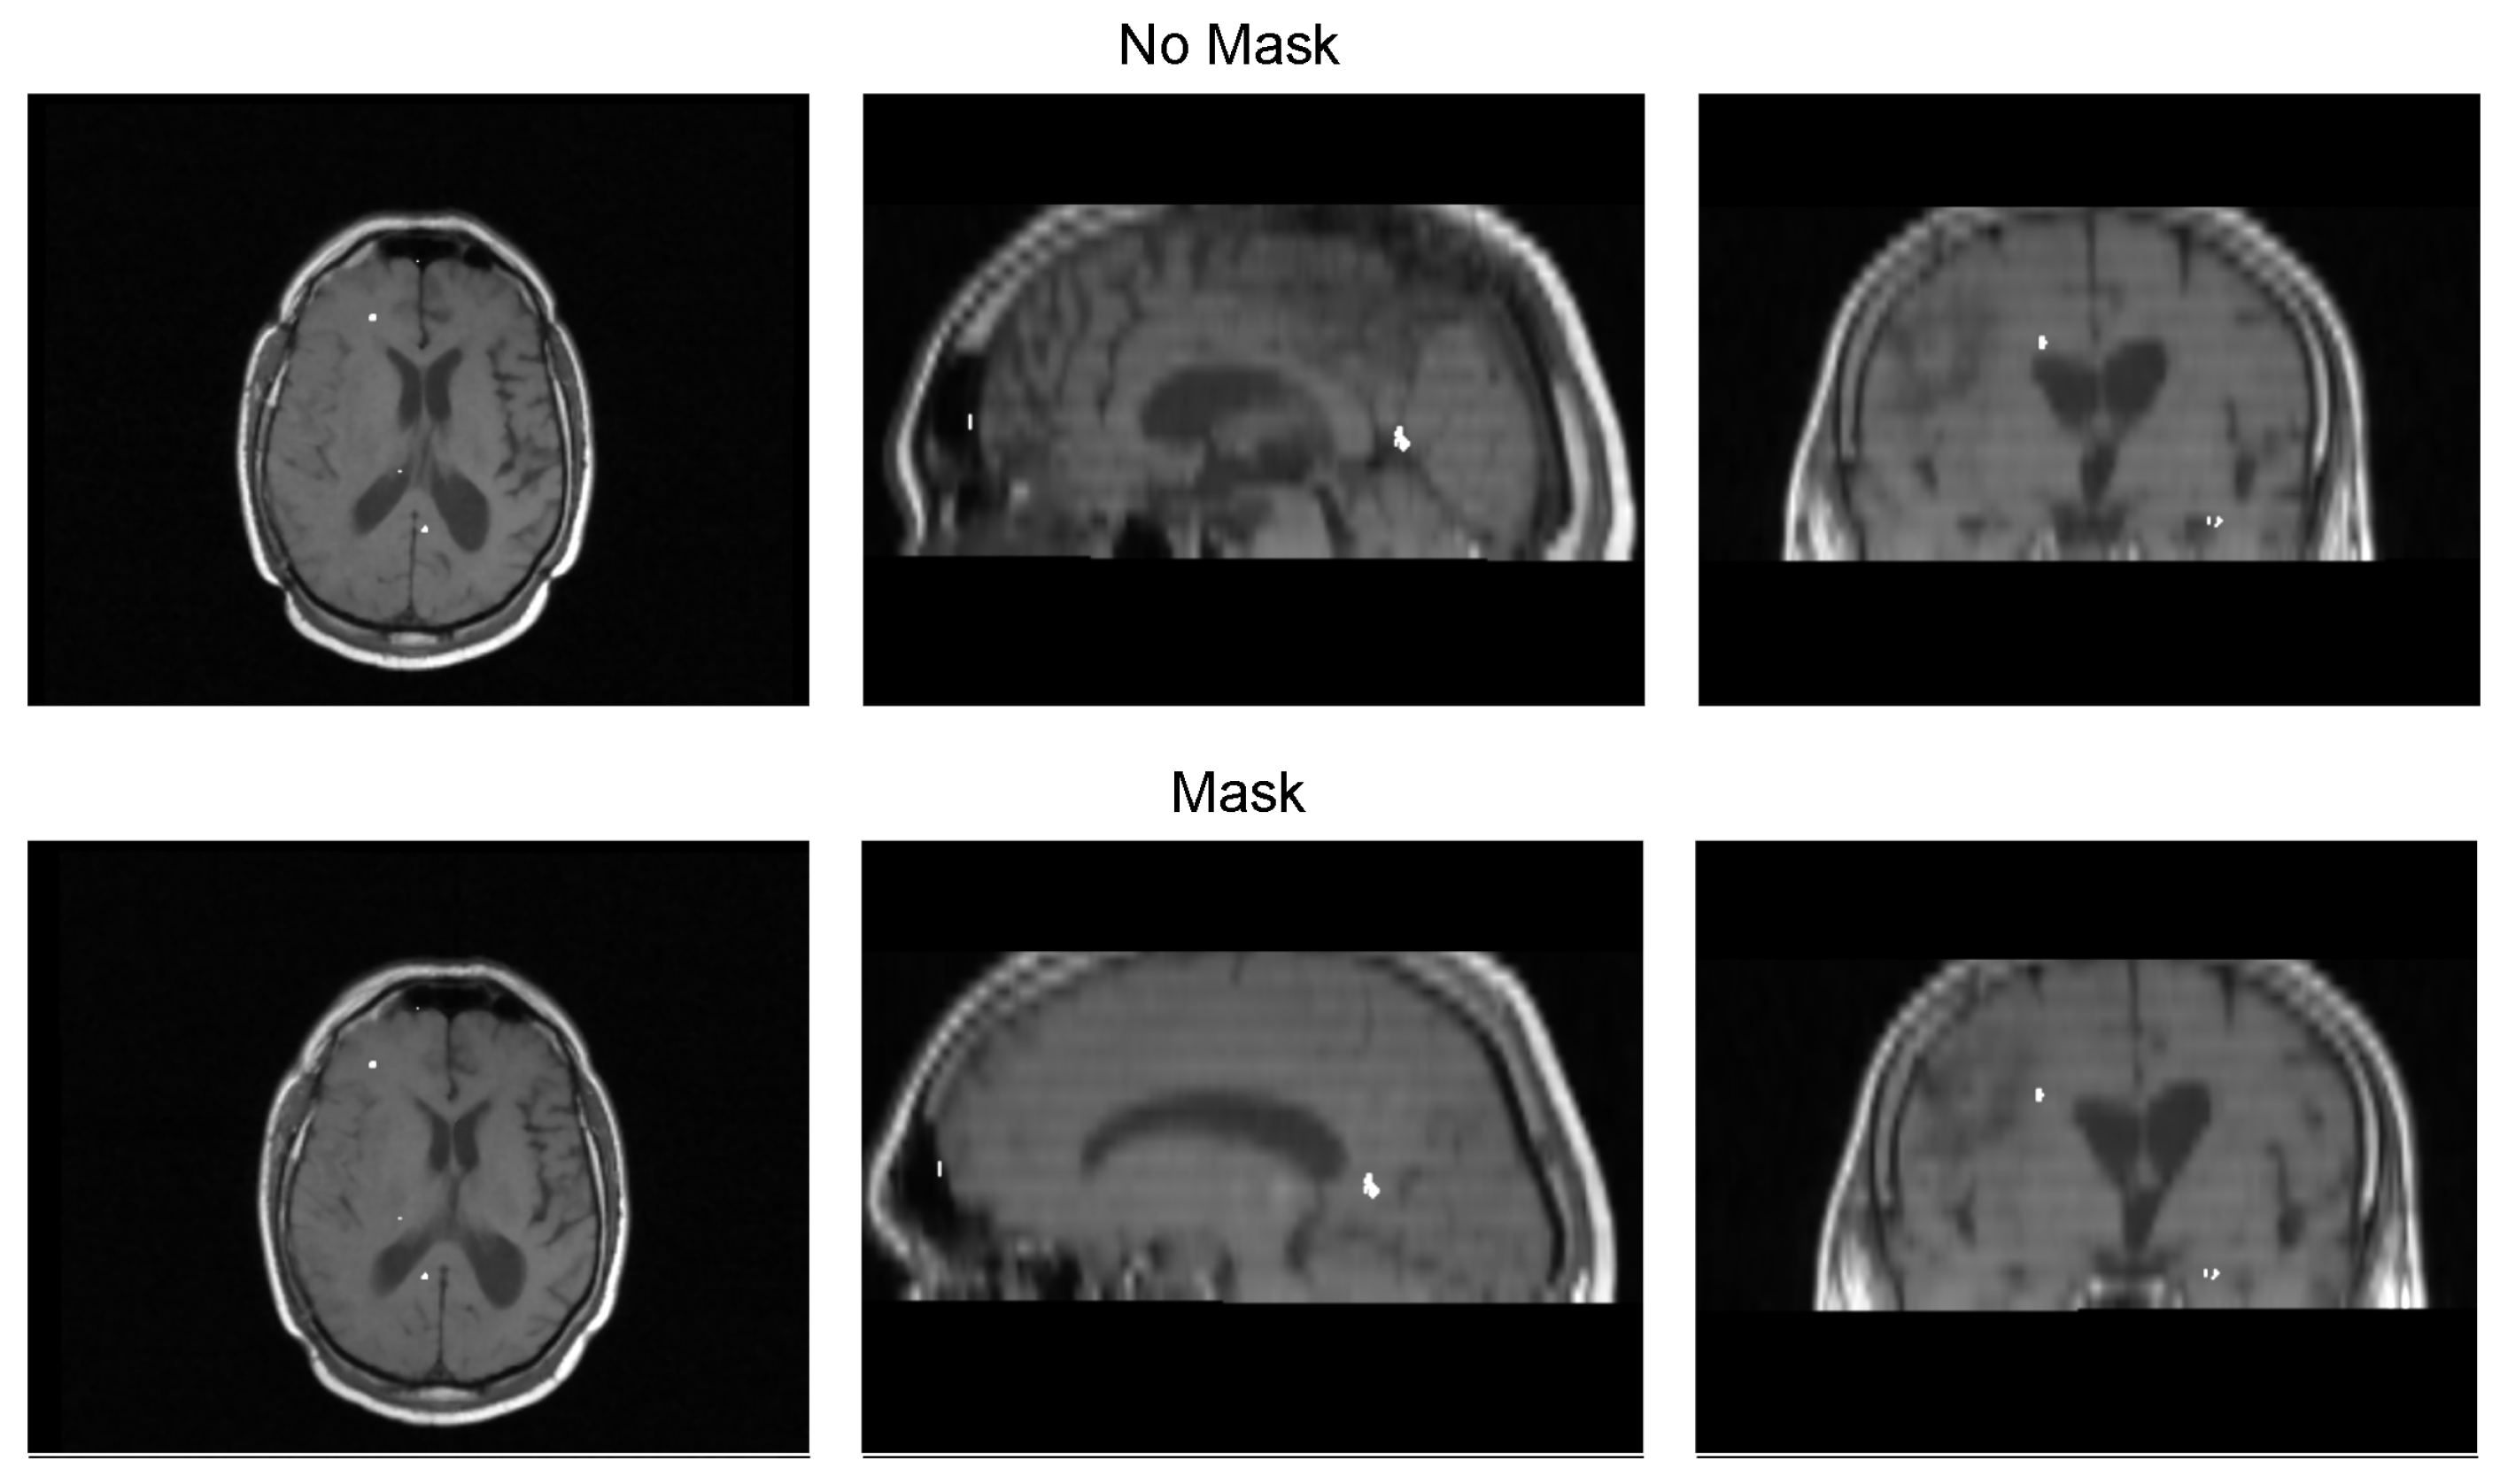

We validated the performance of the fusion method following the two methodologies in Section 3. We used eight pairs of CT and MRI from the RIRE dataset for the first method. The CT images were generated with the method described in Section 3.1.1. We compared the procedure shown in Figure 8 against a fusion procedure that does not employ a sampling mask of the brain tissue, which is shown in Figure 9. Both methods used a rigid registration with MI as the similarity metric and gradient descent for the optimization. We used descriptive statistical metrics of central tendency and variation to compare the methods using the validation from Section 3.1. These results were summarized in the box plot shown in Figure 10. For the second validation, we faced a limitation in the number of images available for evaluation. Given this constraint, we opted to compare the methods individually for each of the four cases. A scatter plot was chosen as the most suitable representation to visualize the error dispersion for both methods. Scatter plots are particularly effective in such scenarios as they allow for clear visualization of individual data points, making it easier to discern patterns or anomalies, especially when dealing with a smaller dataset. This approach provides a more transparent and detailed view of the distribution of errors across the limited set of images. The results of this comparison are illustrated in Figure 11.

Table 3 displays the Euclidean distance between the reference points and the resulting points of the transformation from the compared methods. From the data, we can observe that the difference in the Euclidean distance for our method is significantly lower in images 3, 6, and 8. This is mainly caused by the differences in the original images that have some variations in brain tissue, as shown in Figure 12, Figure 13 and Figure 14. Due to some electrodes passing through these areas with variations, the sampling in the registration does not use these voxels to compute the transformation, thus improving the registration when the mask is used. The results are represented in Figure 10, where our method using a sampling mask yields a Euclidean distance of 1.3176 mm with a standard deviation of 0.8643. In contrast, the method without a sampling mask yields a Euclidean distance of 1.2789 mm with a standard deviation of 5.2511. These findings suggest that the use of the mask improves the registration when there is a great difference in the tissue between the MRI and CT images due to the reduction in voxel sampling of these varying tissues in the registration process.

Figure 13. Image 6 fusion with no mask and with a mask.

Diagnostics 13 03420 g013